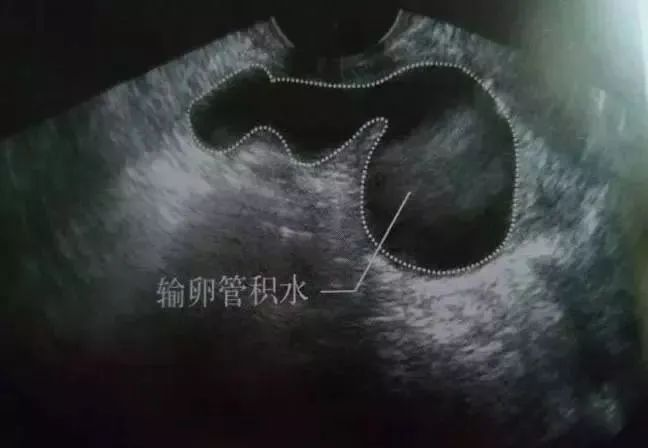

例如「输卵管积水」就是很多女性在备孕过程中经常遭遇的生育难题之一

输卵管积水,是精子过不去的那条河,堵了无数家庭孕育的管道!

B超提示子宫一侧或者双侧出现不规则的液性暗区,呈腊肠状,管内可见异常回声。